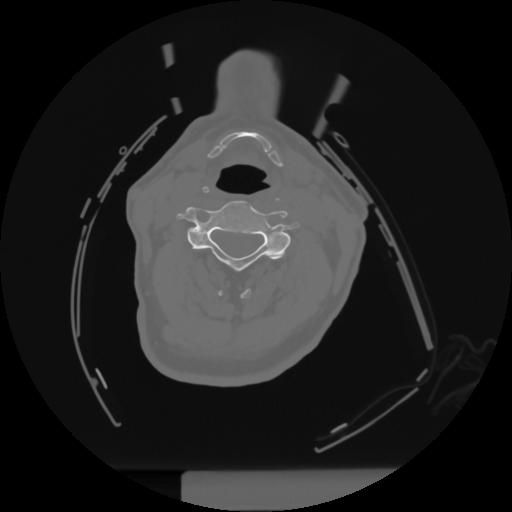

12 P.BLANDAS,,Vol,0.5,P.BLANDAS,,